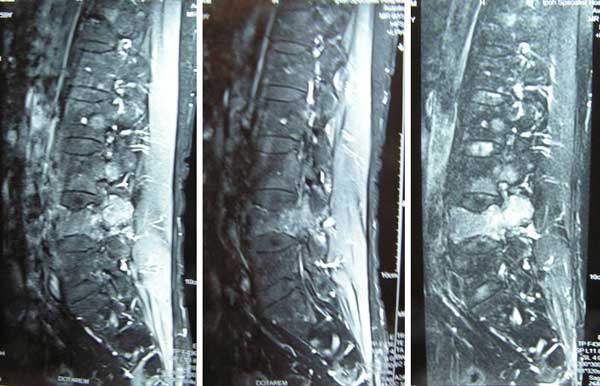

After this Ati returned to Aceh. She started to take the tea made from sour sop leaves for about one and half months. She came back to see her surgeon again for a follow up. MRI done on 8 April 2011 indicated multiple ill define mixed lytic and sclerotic lesions involving the spine – predominantly at the lower thoracic and lumbar spine as well as in the pelvis. These are likely bony metastases.

In December 2011, Ati came back to Penang again. MRI done on 5 December 2011 revealed extensive vertebral metastasis involving the thoracic and lumbar spine. There was a fracture at L4 vertebra and bilateral neuroforaminal narrowing at L4/5 and L3/4.